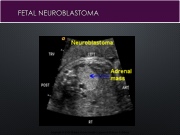

Page 21 - ADRENAL GLAND sono 260